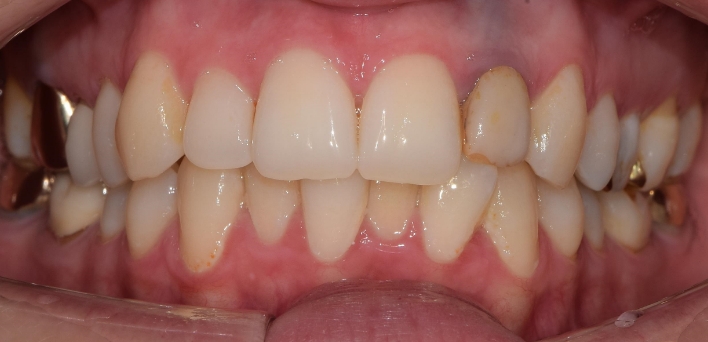

임플란트 : 손 ** 님 (50대)

치아가 있다는게, 아직도 정말 꿈만 같아요.

Before Before

After After

2020.02.30

※ 더서울치과의원은 의료법을 준수하며 위 케이스는 실제 환자의 동의를 얻은 사례로 치료 전, 후가 동일한 환경에서 촬영되었습니다.

환자 케이스에 따라 부작용이 발생할 수 있습니다. 이 부분은 의료진의 충분한 상담과 체크를 통해 예방하고 줄일 수 있습니다.

[임플란트 부작용] 수술 후 관리가 소홀할 경우 출혈, 주위염 등의 부작용이 발생할 수 있어 구강 위생을 철저히 유지하고, 정기적인 검진을 통해 상태를 점검하는 것이 중요합니다.

위, 아래 6개씩 식립

디지털 풀아치 임플란트